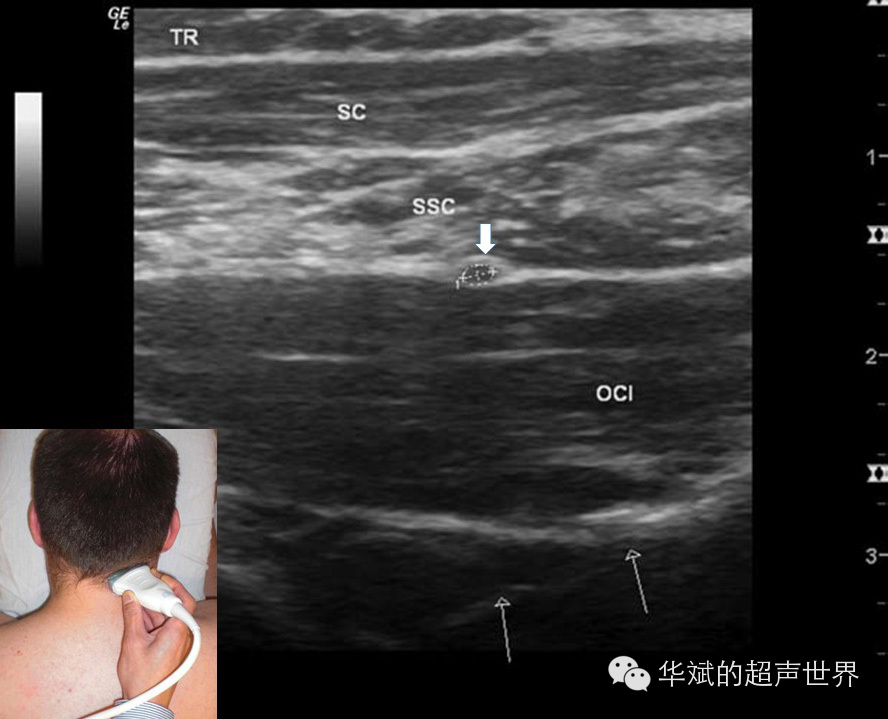

1. 以肌肉作为标志(表二)。外周神经的主干都走形于肌肉筋膜间隙内,因此熟悉每条外周神经毗邻的肌肉结构就可以利用肌肉结构作为神经的标志。例如:枕大神经作为脊神经的分支由椎间孔分出后先下下再向上绕行于头下直肌后方上行。头下直肌是连接枢椎棘突和寰椎横突的一块肌肉,超声检查时非常容易识别,是定位枕大神经的最佳标志(图5)。又如:股外侧皮神经作为腰丛的一支沿盆后壁下行,于髂前上棘水平在缝匠肌和髂肌沟处穿出至皮下。股外侧皮神经是一支细小的皮神经,超声不易直接显示,周围也没有血管伴行,因此在髂前上棘水平显示缝匠肌起点和髂肌即可定位股外侧皮神经(图6)。而肌间沟臂丛神经阻滞则是以前斜角肌和中斜角肌作为标志定位位于臂丛;臀部坐骨神经阻滞则可以以股方肌作为定位标志。

5 枕大神经定位。OCI:头下斜肌,短箭头:枕大神经,长细箭头:椎弓,SSC:头半脊肌,SC:头夹肌,TR:斜方肌